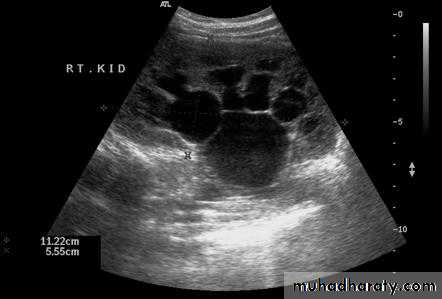

A 27 year old pregnant lady discovered during prenatal U/S to have antenatal hydronephrosis. How would you interfere ?Watchful surveillance

HOW WOULD YOU EVALUATE HER POSTNATALLY ?U/S in the first week of life

WHAT ARE THE POSSIBLE UNDERLYING CAUSES ?PUJ obstruction

PUJ obstruction

U/S : AP diameter of the renal pelvis, kidney size.IVP

CT scanRadionuclide renography : the best radiographic study.

U/SIVP